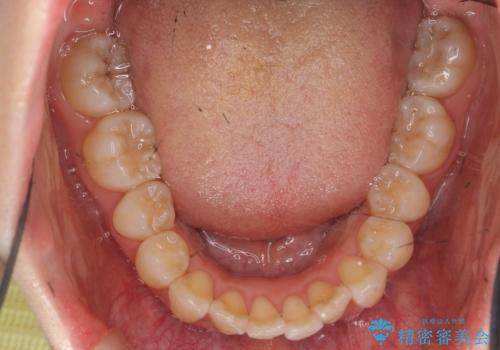

インビザラインで出っ歯の治療

- 「目立つ前歯の出っ歯をなんとかしてほしい。」と矯正治療を希望され来院されました。

突出した上顎の前歯に加え、ガタつきの目立つ下顎の歯列も同時にマウスピース矯正インビザラインで整えていきます。

突出間(所謂 出っ歯)のある前歯の位置は大幅に改善され、審美性が大きく向上しました。

加えて奥歯も噛み合わせも良くなったことで、咬合状態が安定しより安定した歯列を獲得することができました。